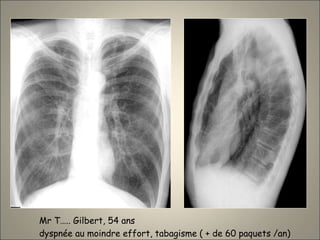

Mr T….. Gilbert, 54 ans

dyspnée au moindre effort, tabagisme ( + de 60 paquets /an)

EPL.

A noter la présence

d’un petit cancer:

AdénoK ( ).